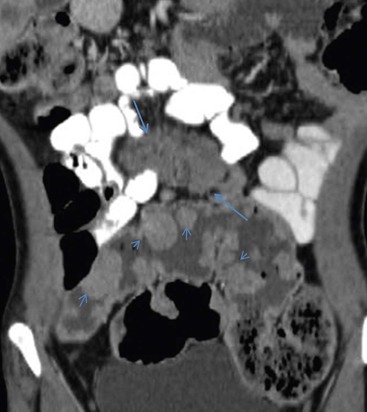

Involvement of the small bowel (SB) and SB mesentery is considered an independent prognostic factor of survival in patients with peritoneal carcinomatosis. The extent of SB/SB mesentery involvement by peritoneal seeding is crucial in the selection process of candidates for CRS and it is also important for surgical planning. Furthermore, SB mesentery is a common location of suboptimally debulked disease after CRS. As opposed to the clinical significance of an accurate preoperative evaluation of peritoneal seeding affecting the SB/SB mesentery, cross-sectional imaging presents the lowest sensitivity and diagnostic accuracy in this specific area. CT enteroclysis with SB distension by negative contrast medium results in increased sensitivity and specificity in the diagnosis of the extent of SB/SB mesentery involvement by peritoneal carcinomatosis36 and it has been proposed in the preoperative work-up in candidates for CRS (Fig. 30-31).